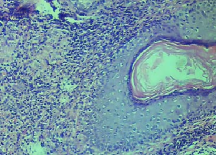

Leishmaniasis background and histology presentation. The World Health Organization (WHO) has selected cutaneous leishmaniasis as a neglected tropical disease (NTD) with growing, uncontrolled, and ignored infection affecting millions of people every year [14, 9]. It is unfortunately one of the world’s most neglected poverty-related diseases, affecting the poorest people in developing countries and it is associated with risk factors like malnutrition, immune system deficiency, migration, inadequate education, illiteracy, gender inequality, and a shortage of services [1]. Furthermore, only eight countries in the world contribute to 90% of leishmaniasis cases: Afghanistan, Algeria, Brazil, Iran, Pakistan, Peru, Saudi Arabia, and Syria [12]. It is a vector-borne infection caused by the protozoan parasite Leishmania. The vector is the female sand-fly. The lesions of cutaneous leishmaniasis vary in presentation ranging from a single self-limited skin lesion to multiple large destructive and ulcerated lesions on mostly the exposed parts of the body such as face, forearms, and lower legs [2]. Skin biopsy is considered the gold standard method for confirmation of diagnosis. The presence of large epitheloid granulomas and small hematoxylinophilic LD bodies (that are round, uniform in appearance, intracytoplasmic and sometimes distributed around the outer rim of the vacuoles) is critical for diagnosis and confirmation of leishmaniasis [4]. Large granulomas are visible at 10X but the smaller hematoxylinophilic bodies (around 3-4mm in size) are usually visible at 40X and can easily be missed if they are few in number, leading to misdiagnosis. Specialized dermatopathologists are the only ones who can diagnose these accurately based on patient history, clinical features, and laboratory diagnosis. It is thus critical to share the digitized slides of these cases from rural poor remote areas with dermatopathologists (mostly residing in urban centers) for quick diagnosis and accurate management of the patient.

We demonstrate our WSI creation workflow on Leishmaniasis cases, as shown in Figures 1 and 4. An expert pathologist reviewed the cases and annotated granulomas as well as LD bodies on the stitched images and our generated images in Figure 4. To show generalizability of our approach, we also show results on core biopsies of breast, duodenum, stomach, liver, and lymph nodes (Figure 5).